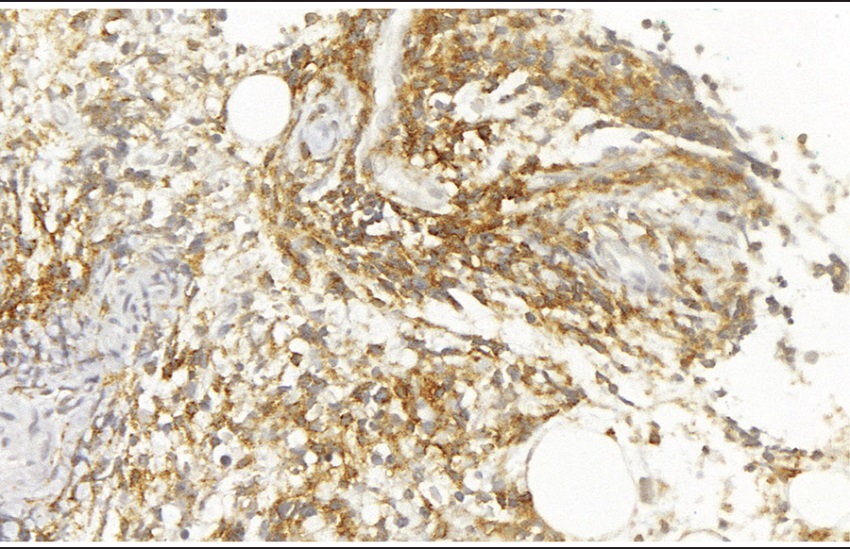

The iliac crest bone marrow biopsy exhibited marked hypercellularity due to an interstitial infiltration by malignant neoplasm with small round cells (Figure 2). There were foci of fibrosis and increased bone marrow reticulin (Figure 3). Immunohistochemical study shows positivity for CD45 (2B11 + PD7/26, Dako, ready for use), CD20 (clone L26, dilution 1:250, Cell Marque), CD79a (JCB117, Dako, ready for use, Figure 4), TdT (polyclonal, Dako, ready for use, Figure 5) and CD10 (56C6, Dako, ready for use, Figure 6), negativity for CD99 (12E7, Dako, ready for use), desmin (D33, Dako, ready for use), CD3 (polyclonal, Cell Marque, dilution 1:150), CD163 (MRQ-26, Cell Marque, ready for use) and CD1a (010, Dako, ready for use). Immunohistochemistry demonstrates positivity for CD45 (Figure 4), CD79a (Figure 5), CD20, TdT and CD10. Morphological and immunohistochemical findings were consistent with the diagnosis of acute lymphoblastic leukemia, immunophenotype B (B-ALL), with a bone primary multifocal presentation, clinically characterized by hypercalcemia, multifocal osteolytic lesions and single cytopenia. The patient received the chemotherapic protocol called BFM-2002 (Berlin-Frankfurt Munster European Group for ALL treatment) but had several clinical complications secondary to treatment and ultimately died after ten months of treatment.

Positivity for CD79a indicates the immunophenotype B of the neoplasm.